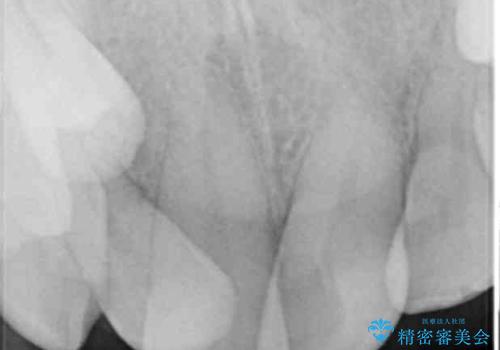

- ぶつけて前歯が折れてしまったとのことで来院された患者様です。

折れてしまった前歯は軽傷であり、歯内の歯髄に影響は及んでいませんでした。

通常では速やかにオールセラミッククラウンにて補綴治療を行うのですが、デコボコしている歯列も気になっていたため、事前に矯正治療を行うこととしました。

上顎歯列の叢生が著しかったため、上顎左右第一小臼歯2本を抜歯し、目立たないワイヤー装置にて治療を進めることとしました。